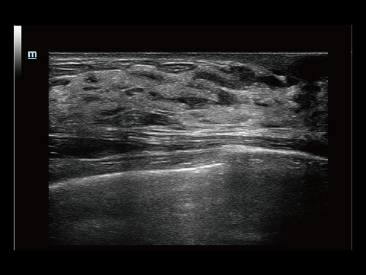

Dank der ZONE Sonography?-Technologie (ZST+) wird das B-Bild des Resona 7 ├╝ber die komplette Tiefe fokussiert, sodass keine Fokuspunkte mehr gesetzt werden m├╝ssen. Die Schall-Lauf-Geschwindigkeit (SSC) wird auf Knopfdruck individuell auf den Patienten angepasst, was die Darstellung von Organen, Grenzfl?chen und Gewebever?nderungen erheblich verbessert. Und dank der fortschrittlichen iFusion-Funktion k?nnen optional die Daten von Ultraschall-, MRT-und CT-Bildern synchronisiert werden.